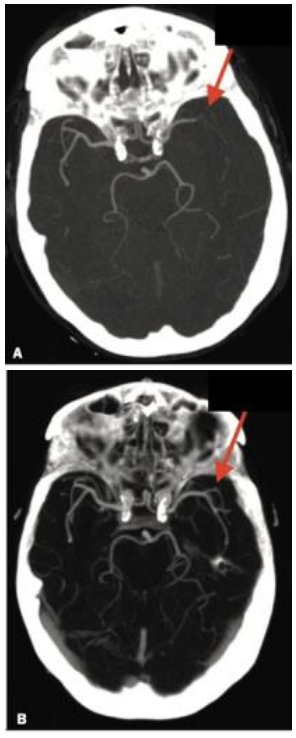

Nessa angiotomografia computadorizada de paciente com acidente vascular encefálico isquêmico agudo pode-se observar

oclusão na bifurcação da artéria cerebral média esquerda (seta da figura A) e recanalização completa após trombectomia (seta da figura B).